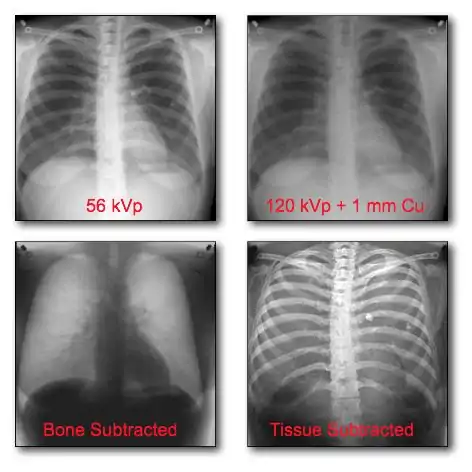

Dual-Energy Imaging